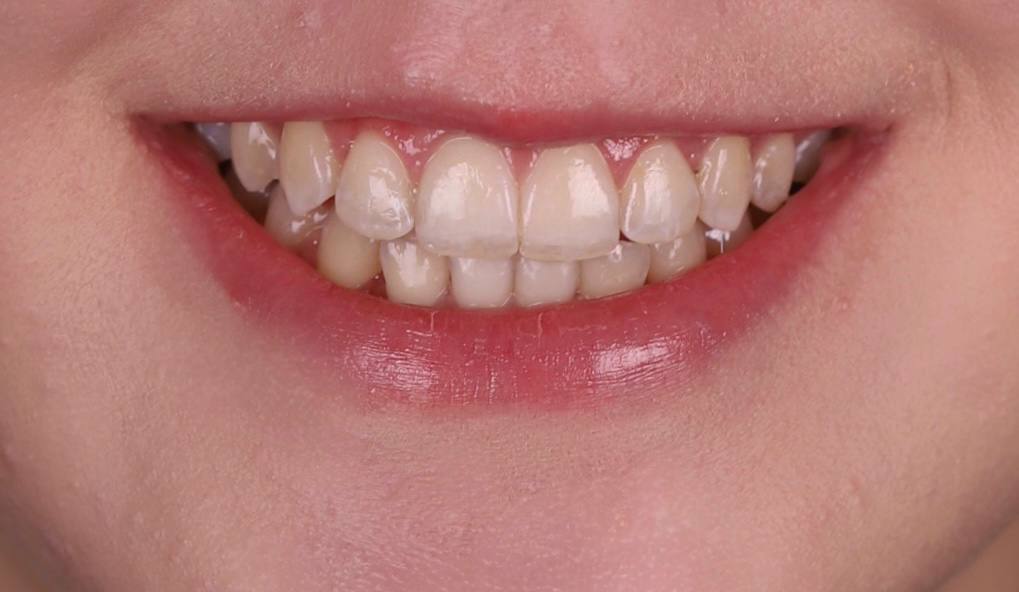

Исправить скученность зубов в зоне улыбки - было моей мечтой! Спасибо клинике ОК и Анастасии Андреевне за воплощение моей мечты в реальность!

Стеснялась улыбаться, потому что один зуб был как будто спрятан назад и казалось, что его нет. Сейчас я счастлива, что могу уверенно улыбаться и моя улыбка мне нравится!